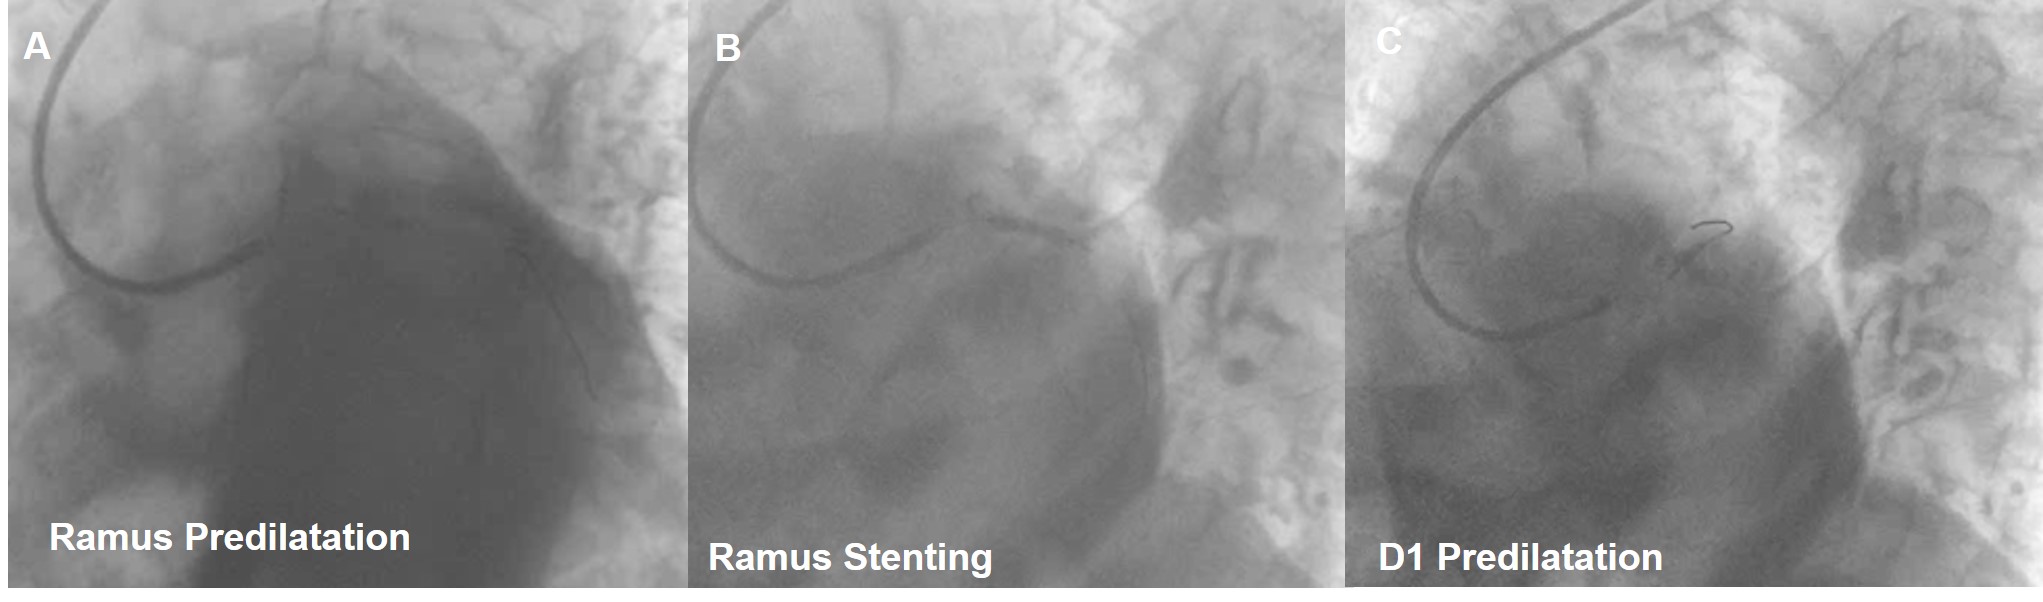

Procedure performedthrough right radial artery LMCA engaged with 6Fr EBU 3.5 Guiding catheter, 0.014X180cmRun-through wire placed in LAD and another Run-through wire was placed in Ramus.Predilatation done with 2.0x12mm Balloon. RAMUS stenting was done with 2.75X18mm Onyx DES. Diagonaldilatation done with 2.0 x 25mm PREVIL Drug Eluting Balloon. Thefinal result was good with TIMI III Flow without any edge dissection andresidual stenosis. Patient was discharged in a stable status on 3rd postprocedure day without any CV Symptoms.